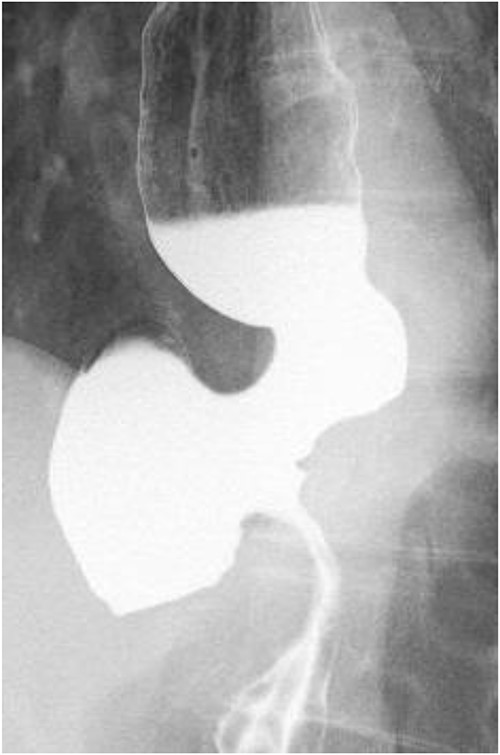

A 60-year-old female with dysphagia and vomiting visited the university hospital. In 2007, she underwent esophageal diverticulum resection (procedure unknown) with a diagnosis of an esophageal diverticulum, which subsequently recurred. In 2011, she underwent a transesophageal hiatus diverticulectomy and a fundoplication (Nissen procedure) at a local hospital. In 2013, dysphagia and vomiting appeared. The patient was diagnosed with recurrence and underwent balloon dilatation for follow-up. In 2015, the patient came to our hospital due to persistent symptoms. After one balloon dilation, the patient did not show any improvement and was referred for surgery. Esophageal fluoroscopy revealed a diverticulum 5 cm in size in the lower esophagus just above the eruption. There was no significant change in the diverticulum size before and after dilation (Figs 1 and 2). Gastrointestinal endoscopy revealed a diverticulum in the lower esophagus, with a residue accumulation (Fig. 3). The esophagus directly below the diverticulum was narrowed. The patient was diagnosed with recurrent lower esophageal diverticulum and underwent surgery.

Preoperative esophageal fluoroscopy (after dilation). There was no significant change compared to the pre-expansion period.